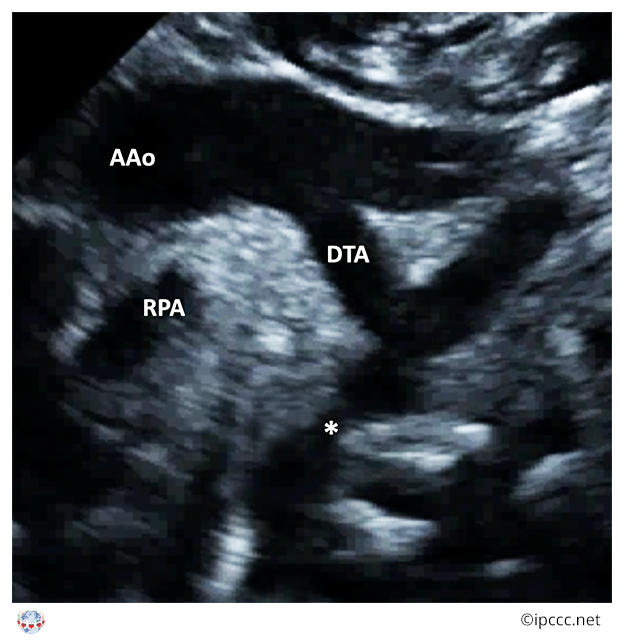

You are here: Coarctation of aorta ⇗ Congenital anomaly of aorta or its branches ⇗ Congenital anomaly of great arteries including arterial duct ⇗ Structural developmental anomaly of heart or great vessels

A congenital cardiovascular malformation in which there is a discrete luminal narrowing of the junction between the aortic arch and the descending aorta.

Coarctation of the aorta generally indicates a narrowing of the descending thoracic aorta just distal to the left subclavian artery. However, the term may also be accurately used to refer to a region of narrowing anywhere in the thoracic or abdominal aorta.

Echocardiogram